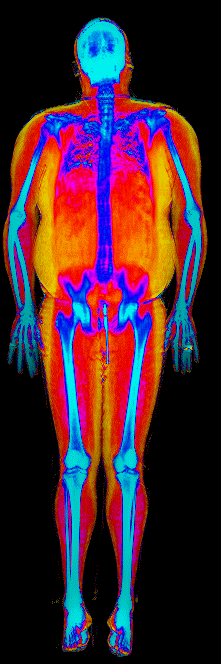

This page features real, anonymized DEXA scan images from BodyStats clients, organized by gender and body fat percentage in 5% increments. DEXA (Dual-Energy X-ray Absorptiometry) is the clinical gold standard for measuring body composition — far more accurate than scales, calipers, or visual estimates.

Each colorized scan shows the distribution of fat tissue (shown in warmer colors) and lean tissue (cooler colors) throughout the body. Compare your own DEXA scan to others in your range, or see what different body fat levels actually look like on a scan.

Female DEXA Scans by Body Fat %

40 to 45% body fat